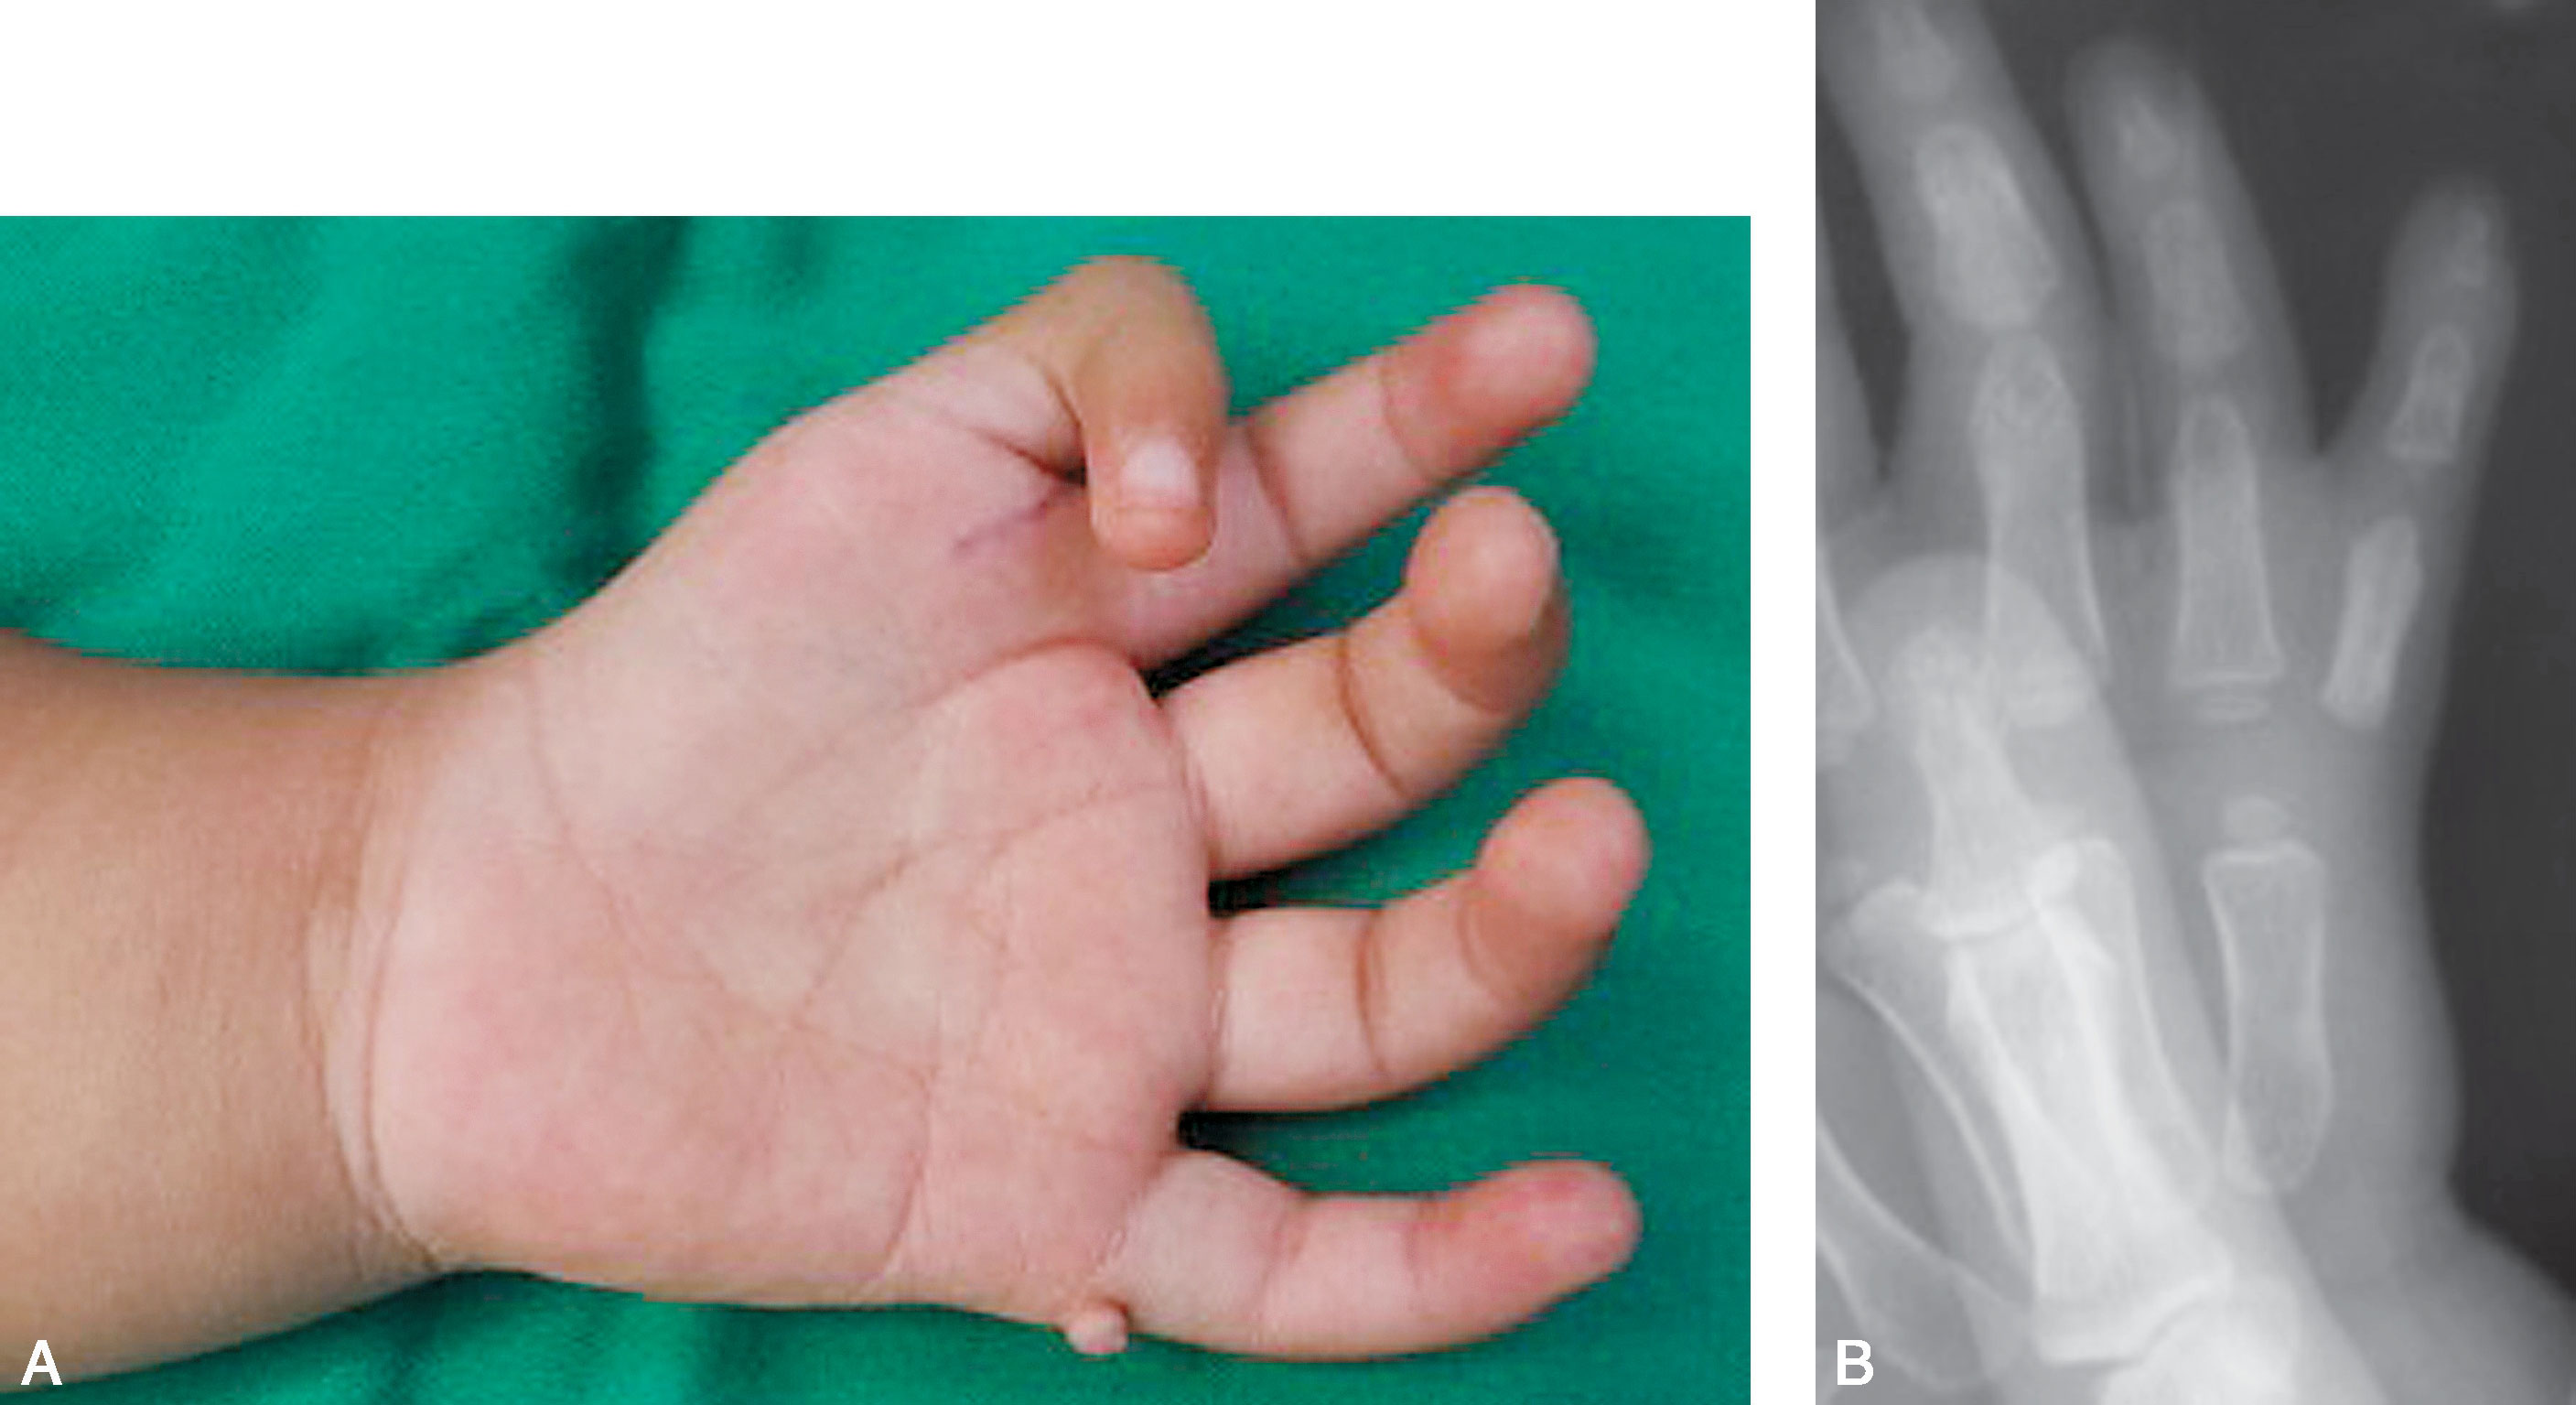

图1-2-2 先天性缺指病例

A.左侧先天性手示、中、环指掌指关节水平缺如,小指远侧指间关节桡侧“肉赘样”赘指;B.X 线片显示示、中、环指掌指关节以远骨关节结构未发育